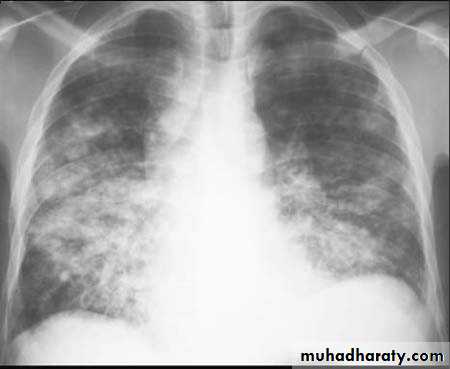

2-Bronchopneumonia

refers to more patchy alveolar consolidation associated with bronchial and bronchiolar inflammation often affecting both lower lobesCommunity-acquired pneumonia (CAP)

@Radiological examination usually provides confirmation of the diagnosis. In lobar pneumonia, a homogeneous opacity localized to the affected lobe or segment usually appears within 12-18 hours of the onset of the illness. Radiological examination is helpful if a complication such as parapneumonic effusion, intrapulmonary abscess formation or empyema is suspected :@Sputum: direct smear by Gram and Ziehl-Neelsen stains. &Culture and antimicrobial sensitivity testing